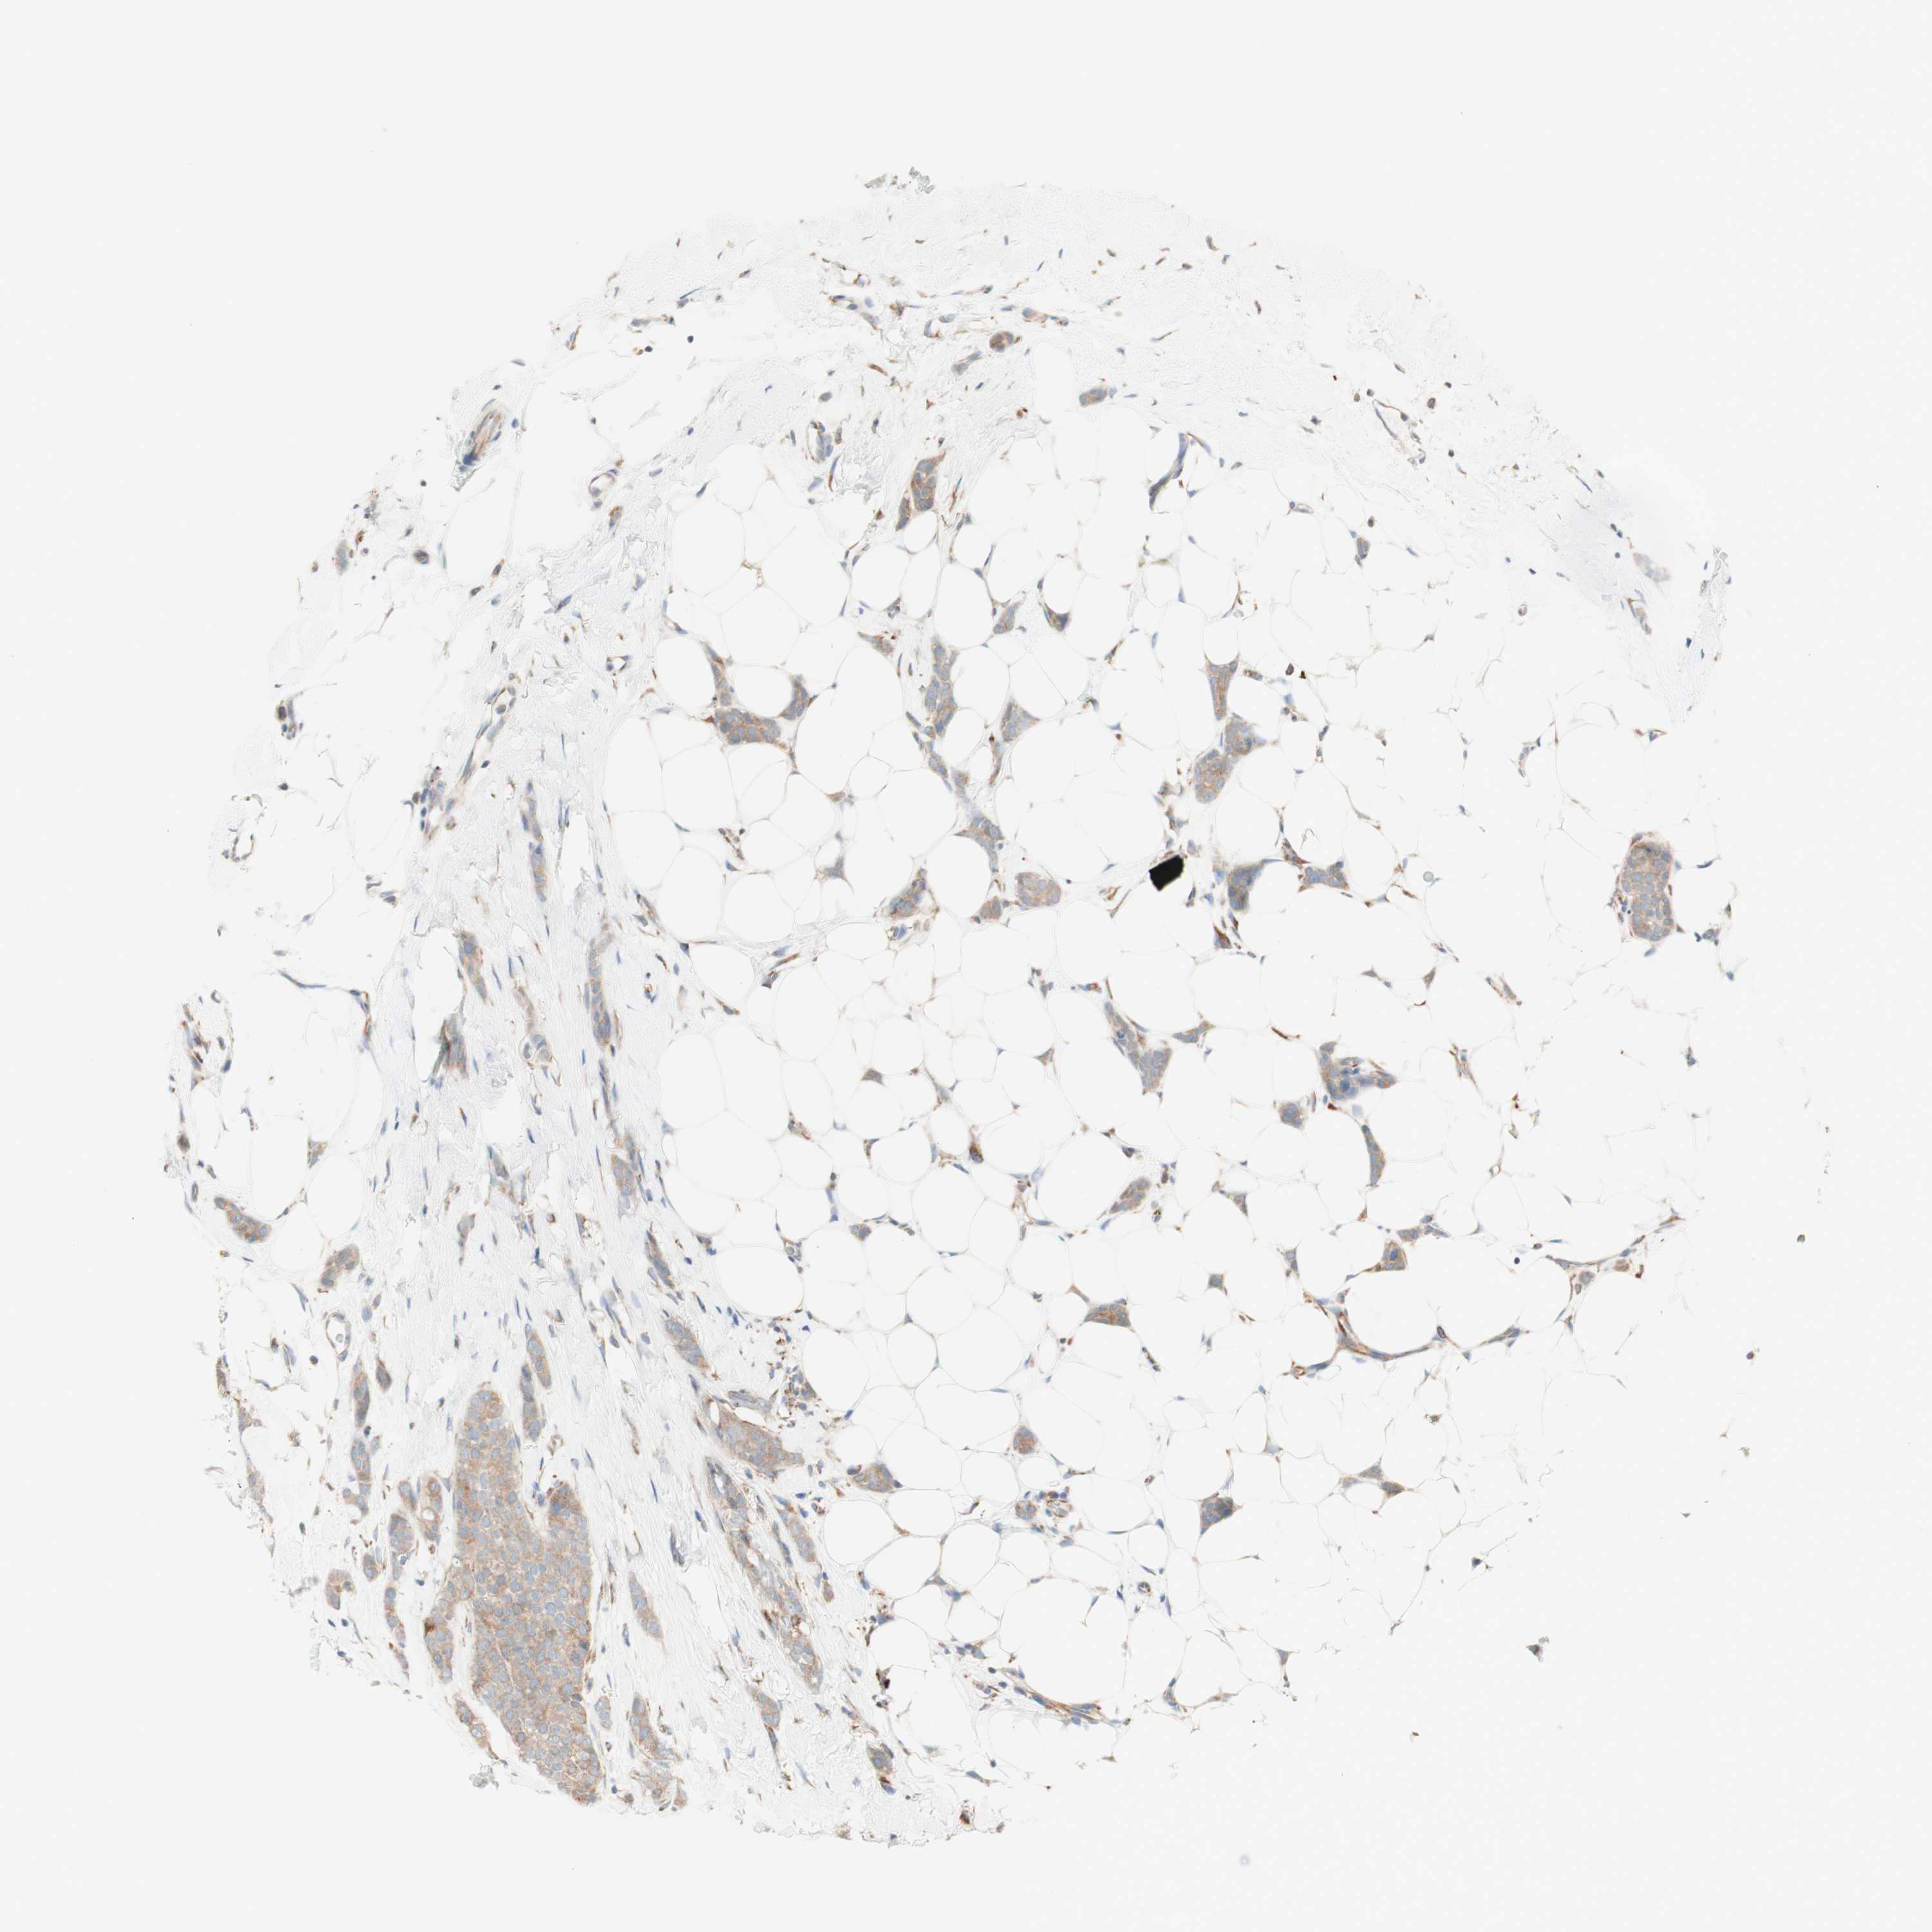

CANCER BREAST CANCER Show tissue menu

BRCA TCGA BRCA VALIDATION PROTEIN EXPRESSION

ANTIBODIES

AND

VALIDATION